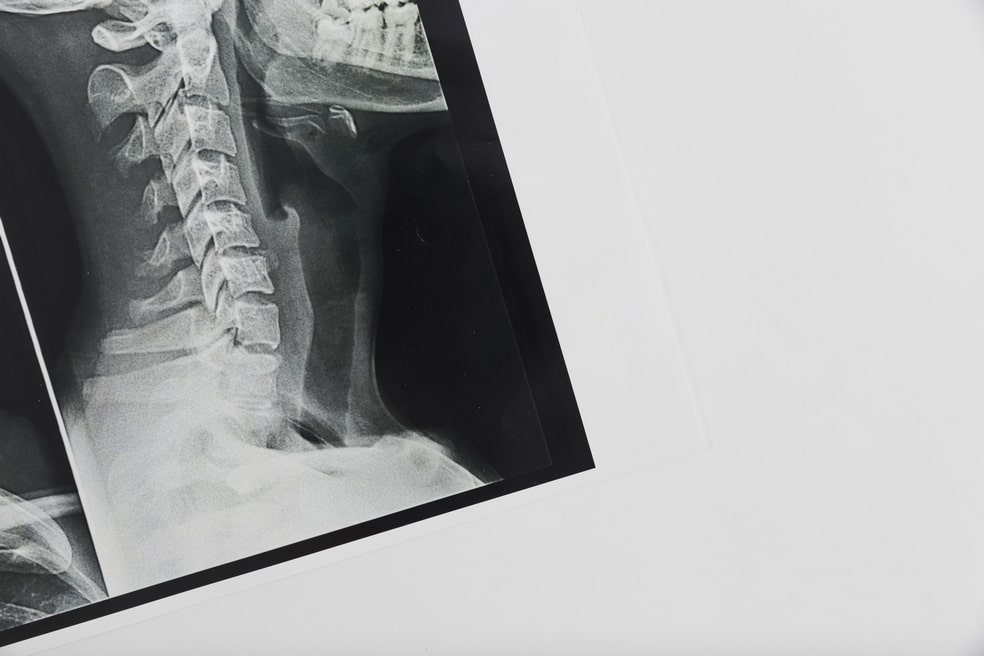

МРТ шейного отдела позвоночника

МРТ шейного отдела позвоночника Источник фото https://ru.freepik.com/, автор @freepik

Шея – наиболее подвижный и уязвимый отдел позвоночника. Травмы и патологии в шейном отделе негативно влияют на работу мозга, так как кровеносные сосуды, предназначенные для его питания, расположены именно в шее. МРТ шейного отдела позвоночника выявляет патологические изменения костных и мягких тканей, позволяя оценить состояние мышц, связок, сосудов, обнаружить воспалительные процессы или опухоли.